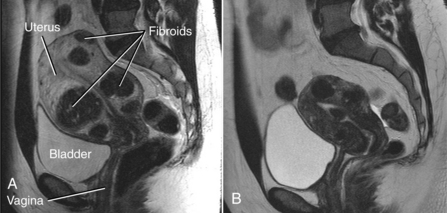

Fibroids can and often do grow to the size of a grapefruit or larger. Growth is related to estrogen and possibly progesterone; fibroids often regress after menopause. Fibroids can place pressure on the bladder resulting in constipation, urinary frequency, and nocturia. Pressure on spinal nerves can also cause low back pain (Fig. 20-4).

Figure 20-4 Uterine fibroids. A, MRI image of uterine fibroids. Note the position in relation to the sacrum, bladder, and pubic bone. Pressure on nerves and soft tissue in this area can cause painful pelvic, abdominal, low back, and sacral pain. B, MRI image of fibroids after uterine fibroid embolization (same patient). (Courtesy Robert L Vogelzang, MD, Chicago.)